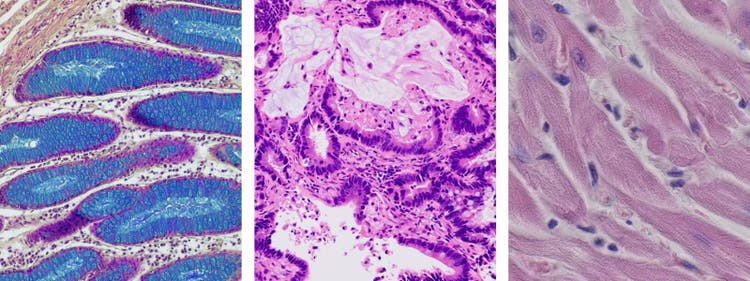

明視野観察では、細胞や組織から鉱物、線維までさまざまなサンプルを研究できます。このことから、多くの研究・産業分野に適した多用途性のある手段となっています。

明視野観察の主な注意事項は、うまく観察できるサンプルが背景に対して高いコントラストを持つものに限られる点です。例えば、透明なサンプルや背景と同じ色であるサンプルは、観察が困難です。また、適切な調製や染色が行われていないサンプルは、明視野顕微鏡で観察できません。